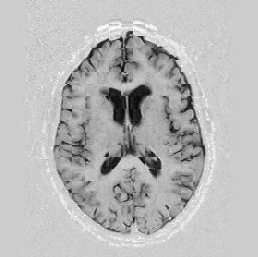

Another larger group of experiments enabled me to study the effects of multi-scale NRR. The results are shown in the form of chequerboard images in Figure [*]. In terms of resolution levels, higher numbers mean that the images are coarser.

Figure: Multi-scale NRR (increasing resolution). From left to right, top then bottom:before NRR; after 5 iterations of NRR at level 2 (higher is coarser); after another 5 iterations of NRR at level 1.